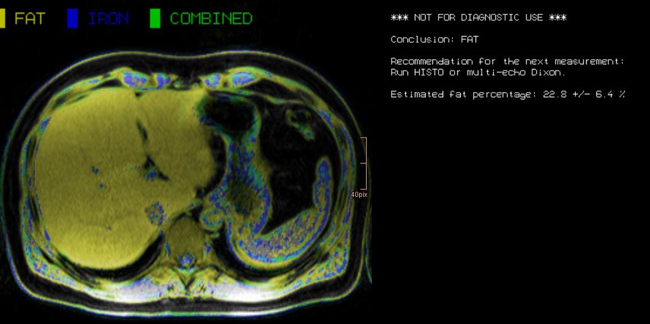

Abdominal MR Imaging

Michaela Plaikner, Benjamin Henninger, Christian Kremser

Morphological and functional MRI in all-organ systems development of novel MRI applications and MR sequences. Examples of research projects: fat, iron or combined disease; influence of iron on the evaluation of liver fat.

a) MRI for the evaluation of diffuse liver disease:

evaluation of different MRI methods (relaxometry, chemical shift imaging, multi-echo approach, Dixon screening), in order to detect diffuse liver disease (fat, iron or combined disease); influence of iron on the evaluation of liver fat.